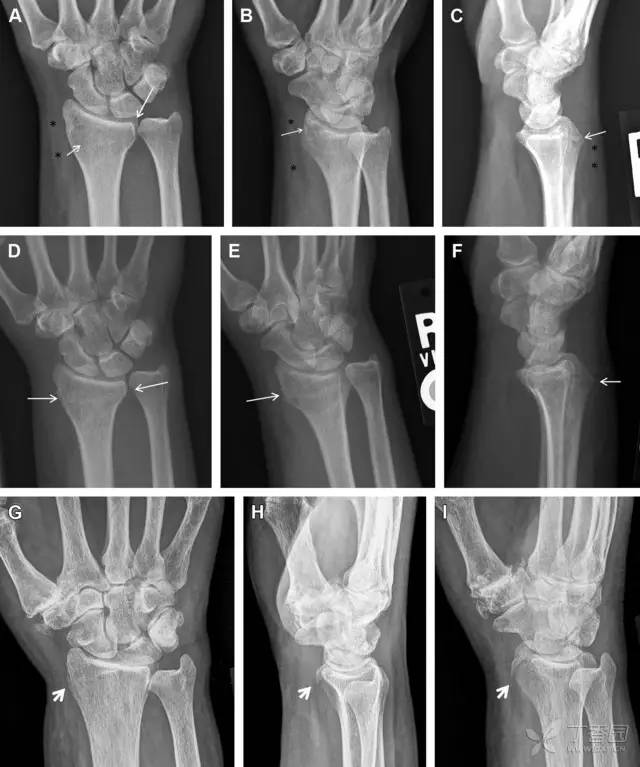

30 桡骨远端骨折

常规进行前后位、侧位、斜位 X 线检查,对于大多数桡骨远端骨折来说不容易漏诊;但是对于无移位的骨折,特别是桡骨茎突骨折,容易漏诊。桡骨茎突骨折是一斜行的骨折,常累及关节面,常发生于轴向应力或直接打击。

图 1 57 岁女性,摔倒后手掌撑地,桡骨茎突压痛。(A~C)前后位、斜位、侧位片示软组织肿胀(*)和发丝样骨折(白色箭头);(D~F)2 周后,前后位、斜位、侧位片示骨折线显明,由于新骨痂沉积而呈现透亮线与硬化线并存;(G~I)另一患者,桡骨茎突骨折在前后位及侧位片上显示不明显,而在斜位片显示更清楚